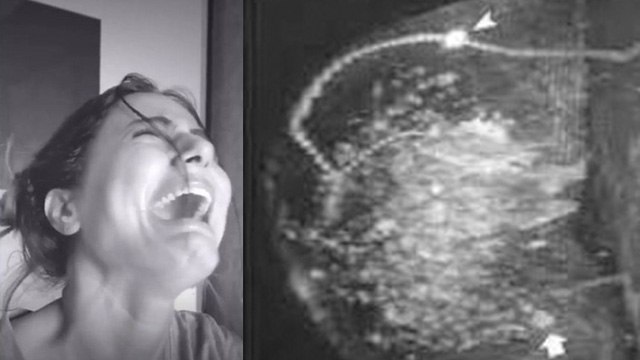

Television actress Hina Khan, who recently informed her fans that she is diagnosed with stage 3 Breast cancer, is currently undergoing treatment for the same. The question arises why more younger women are being diagnosed with Breast cancer across the world. Does this mean that Breast screening should be taken up early? Should gene testing be done? Or should women look into their lifestyles a bit more? Can wearing a bra to bed increase your risk of Breast cancer?Watch Exclusive Interview of Dr. Meghal Sanghavi, Oncosurgeon,, WOckhardt Hospitals, Mumbai Central on Breast Cancer Symptoms, Treatment Chemotherapy Hair Loss, To Shave or Not to Shave and Much More. #HinaKhan #HinaKhanNews #HinaKhanBreastCancer ~PR.126~ED.348~HT.334~